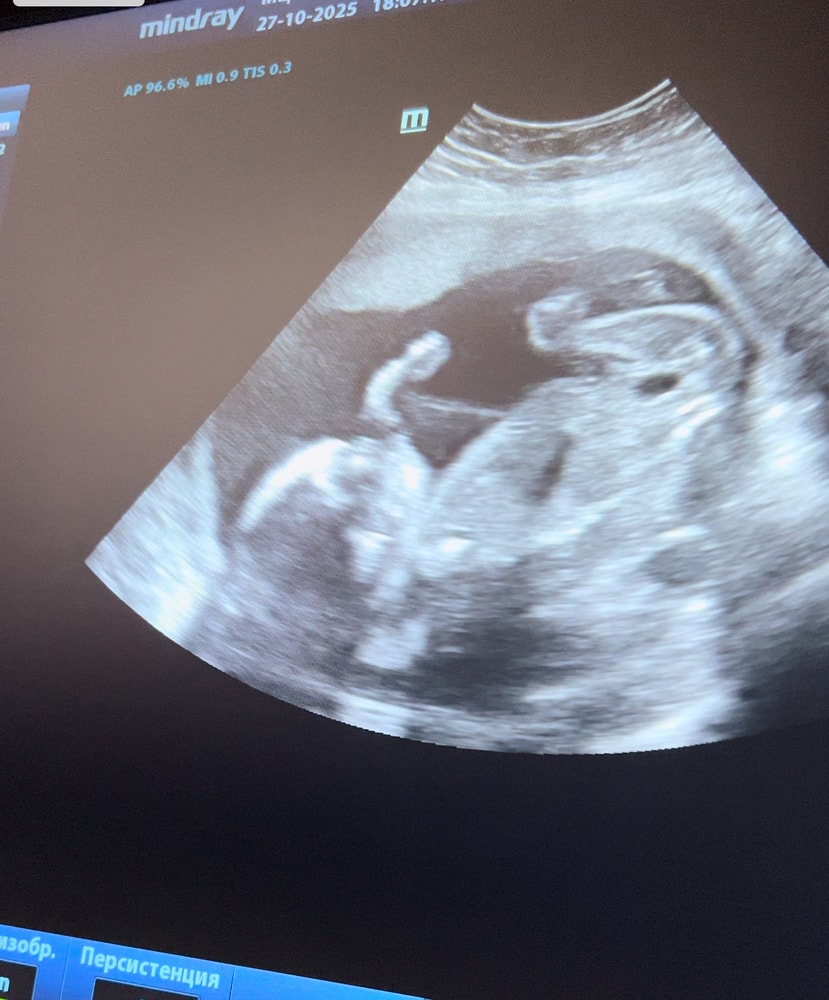

21 неделя) полет нормальный

Сегодня была на узи, сдавала анализы. Мой нервяк, это спокойный ребенок) после дочери, та уже в утробе такое вытворяла 🤣 мой мальчик кажется мне каким то неестественно спокойным🤪 надеюсь после рождения он и останется спокойным😅 все у малыша хорошо) сердечко отличное, размеры хорошие вес 480гр😌 лежит ручкой махает))) потом взял пальчик стал сосать))) ну что за милость 🥰 голодный был) после узи покормила мужичка☺️